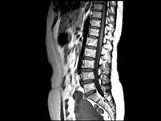

- 单项选择题女,37岁, 下腹部不适,MRI检查如图所示, 下列说法错误的是 ( )

A、子宫底部局部隆起,该病灶边界清晰

B、病灶T

WI信号与子宫肌层的信号相同C、病灶T

WI信号为明显低信号D、此为子宫粘膜下肌瘤

E、此为子宫浆膜下肌瘤